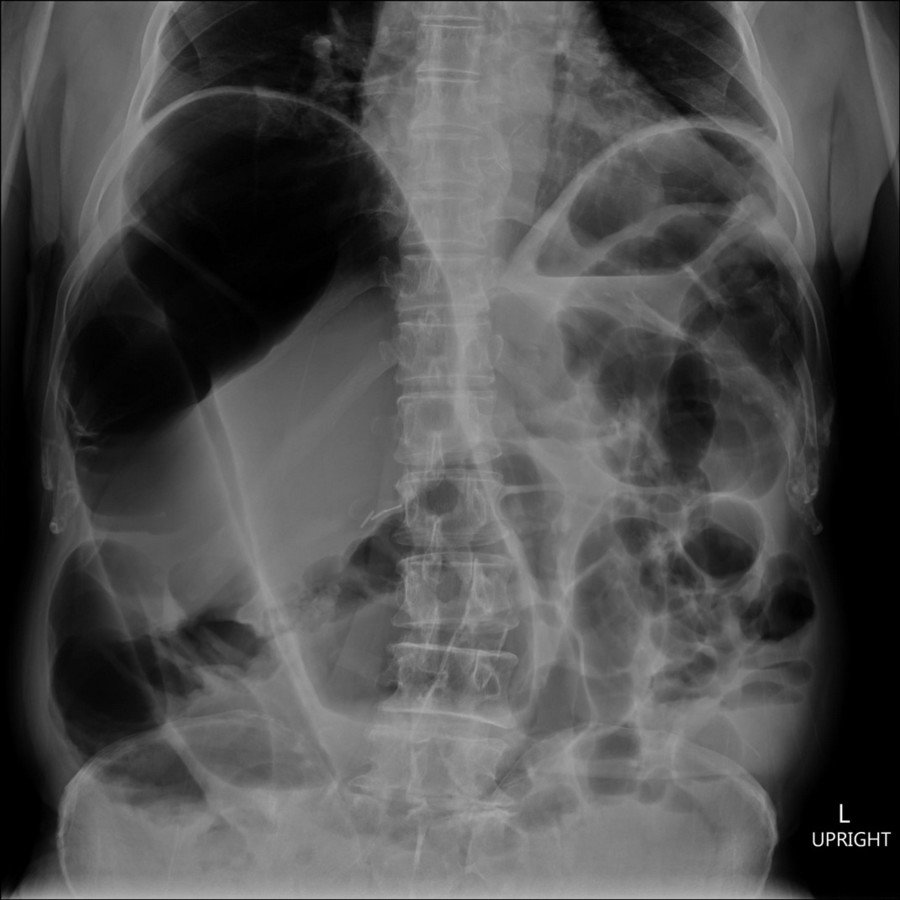

History :  A 76-year-old man with abdominal pain and vomitting.  An abdominal x-ray was performed on admission.

The following signs are included in the abdominal x-ray:

• Coffee bean sign

• Frimann Dahl's sign : Three dense lines converge toward the site of obstruction

• Absent rectal gas

• A classic inverted U-shaped dilated sigmoid colon directed toward the diaphragm